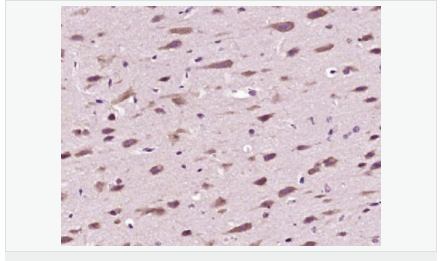

| 產(chǎn)品應(yīng)用 | ELISA=1:5000-10000 IHC-P=1:100-500 IHC-F=1:100-500 IF=1:100-500 (石蠟切片需做抗原修復(fù)) not yet tested in other applications. optimal dilutions/concentrations should be determined by the end user. |